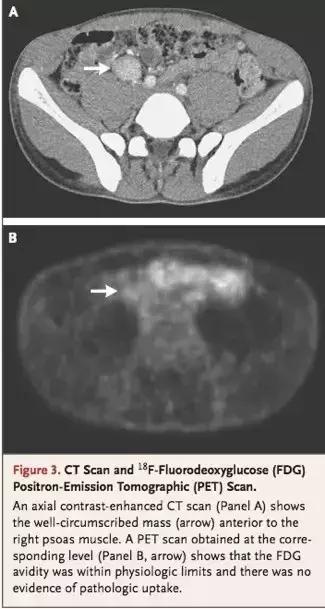

CT与PET进一步确认右侧腰大肌附近的边界清晰的包块